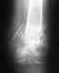

33 года, рост 176, вес 65.В 2013г. открытый оскольчатый перелом б\б кости, год и два месяца проходила в АВФ, несколько раз делали компрессию, в октябре того же года выполнена продольная кортикотомия б\б и косая остеотомия м\б кости, следствии чего кость укоротилась на 3-3,5 см.

После снятия АВФ патологической подвижности в месте перелома не наблюдалось, умеренная нагрузка на ногу, ходила опираясь на трость, через пол года поставили д-з ложный сустав. Подвижности не наблюдаю, присутствуют острые боли. Предстоит операция, для прижатия отломков друг к другу и соответственно ещё укорочение кости. Подскажите, посоветуйте, пожалуйста, возможно ли лечение л.с. и одновременно устранить укорочение конечности? Какие способы эффективней АВФ, Штифт или другое? Сколько ещё займет времени? Можно ли вообще жить с ложным суставом? Заранее благодарна!